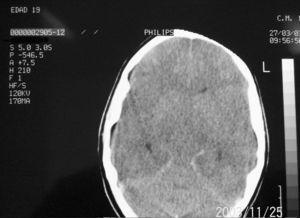

Mujer de 19 años de origen norteamericano, con antecedentes de meningitis por Haemophilus influenzae en la infancia sin secuelas neurológicas. Acude a Urgencias por un cuadro de cefalea intensa, fiebre no termometrada y síndrome catarral los días previos. En la exploración física destaca ligera agitación psicomotriz, sin focalidad neurológica. No presenta rigidez de nuca ni lesiones cutáneas. La analítica muestra 12.600 leucocitos (85% de neutrófilos, el 6% linfocitos y el 9% monocitos) y la punción lumbar 32 células (80% de polimorfonucleares y el 20% de mononucleares), glucosa 60 mg/dl y proteínas 24 mg/dl, compatible con meningitis aguda bacteriana. La tomografía axial computarizada craneal sin contraste fue normal. La enferma empeora neurológicamente durante su estancia en Urgencias, con aumento de la cefalea, vómitos y crisis comicial tónico-clónica con disminución del nivel de conciencia, por lo que se administra 10 mg de diazepam intravenoso y se procede a intubación orotraqueal y conexión a ventilación mecánica. Tras su ingreso en la Unidad de Cuidados Intensivos (UCI) se inicia tratamiento con aciclovir 600 mg/8 h; ceftriaxona 2 g/12 h; vancomicina 1g/12 h y ampicilina 2 g/4 h junto con dexametasona 9 mg/6 h y fenitoína 150 mg/8 h. A las tres horas presenta inestabilidad hemodinámica, junto con episodio de bradicardia seguido de taquicardia sinusal, poliuria y datos analíticos compatibles con diabetes insípida. En la exploración neurológica (sin nueva dosis de sedación tras la administración de diazepam al ingreso) se objetiva coma con escala Glasgow 3, con pupilas midriáticas y arreactivas. Se realiza nueva tomografía axial computarizada craneal que muestra edema cerebral difuso (fig. 1), por lo que se intensifican las medidas antiedema sin conseguir revertir la situación. Ante la sospecha de muerte clínica encefálica se realiza electroencefalograma que refleja ausencia de actividad bioeléctrica. El estudio microbiológico del líquido cefalorraquídeo identifica N. meningitidis W-135. El análisis inmunológico confirma un déficit del complemento, la fracción C1q 7,5 mg/dl (límites normales 10-25), no conocido previamente por la paciente o su familia.

Figura 1. Tomografía computarizada de cráneo.